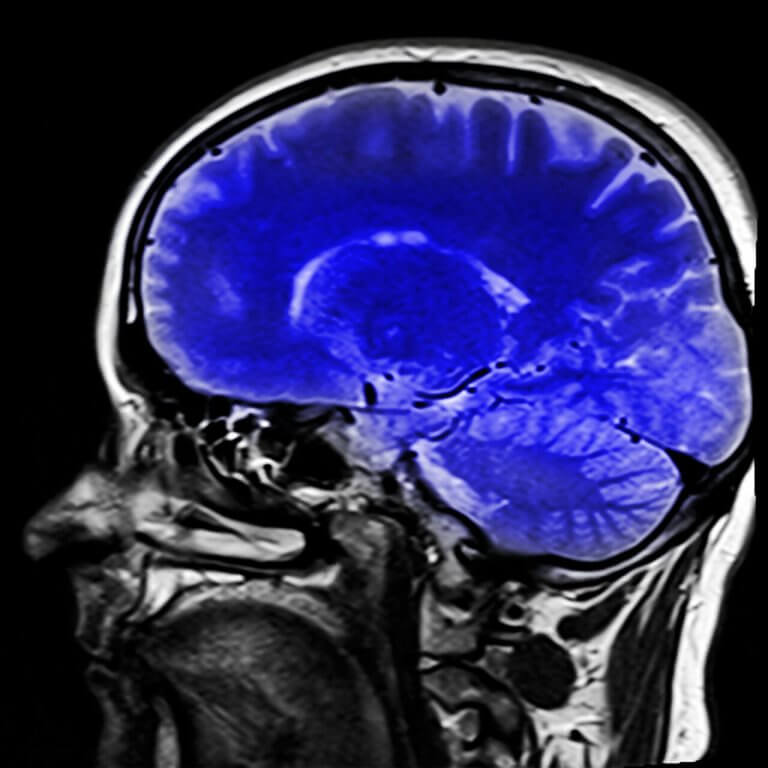

Il existe des tests neurologiques qui aident à établir un diagnostic. L’IRM peut montrer le type de lésion cérébrale qui peut diriger ou non vers un diagnostic du locked-in syndrome.

Aussi bien la tomographie par émission de positons (TEP) que l’électroencéphalogramme (EEG) peuvent renseigner sur l’activité cérébrale. Au travers de la TEP, on peut observer si le métabolisme cérébral est normal, et si c’est le cas, cela voudrait dire que les fonctions cérébrales seraient conservées et qu’il existe une conscience du syndrome.